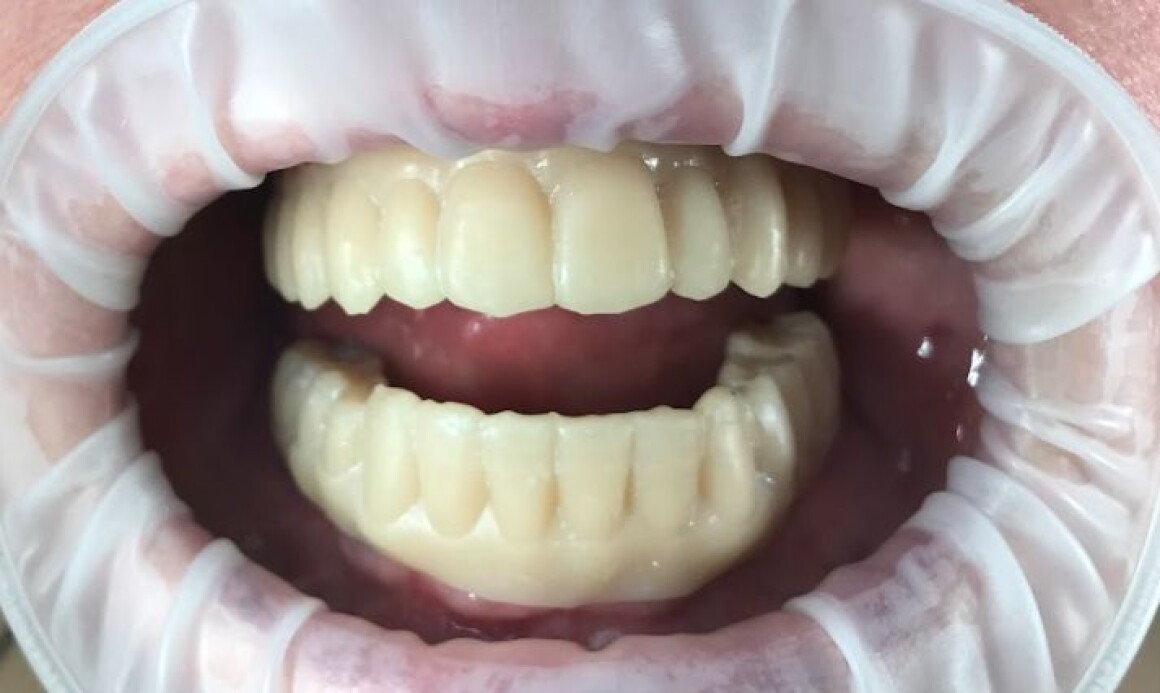

Тотальная реабилитация

Проблема : Полное отсутствие зубов, не держаться протезы

• Имплантация 12 имплантантов за один раз

• Установка временных коронок на имплантантах

• Установка постоянной конструкции из металлокерамики верх и низ